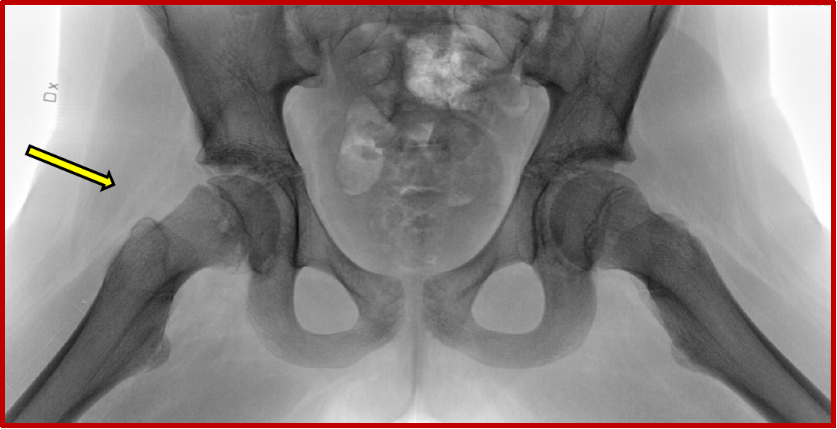

Det finns tre olika typer av höftfyseolys. Förutom att mäta glidningsvinkelns storlek (https://spoq.registercentrum.se/stod-for-vardpersonal/hoftfyseolys-scfe/hoeftfyseolys-definitioner-och-maetmetoder/p/rJaOxuge-) samt värdera symptom utifrån anamnes och statusfynd, behöver man på bra röntgenbilder (bäckenfrontal och sida enligt Lauenstein med båda höfterna avbildade) särskilt noga även värdera det helt fysnära området anteriort på metafysen där en liten avrundning ofta ses om man följer collums anteriora kant fram till fysen. Fysen är ofta också något vidare än i den kontralaterala höften (se bild).